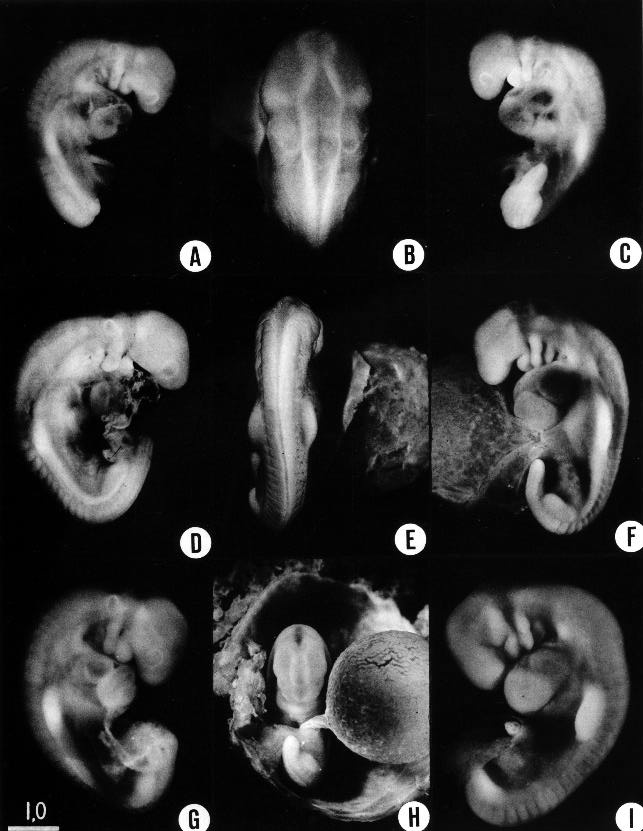

Fig. 13-1. (A–C) Embryo No. 6473 is among the less advanced embryos of the group and is on the borderline of the preceding stage. Because of the translucency of its tissues, much of the internal structure can be seen, particularly the details of the cardiac and hepatic regions. Aortic arches 2 and 3 course obliquely through their respective pharyngeal arches, and it can be seen that the form of the latter is not simply caused by the presence of the arches. The trigeminal and vestibulofacial ganglia, as well as the otic vesicle, can be seen in A. B is a “top” view showing the high degree of specialization of the different parts of the brain wall, and also the attachment of the trigeminal and vestibulofacial ganglia, along with the otic vesicle. Cavity of fourth ventricle is deeper and narrower than appears in the photograph.

(D) Embryo No 6469, showing especially well the optic evagination, the otic vesicle, and the condensed unsegmented mesenchymal strip, extending caudalward from the upper limb bud and probably supplying the body wall musculature.

(E,F) Embryo No. 8066, showing a straighter posture than usual. The form of the upper limb buds is seen particularly well in E.

(G) Embryo No. 7433. The roof of the fourth ventricle is thinner in two areas, which are separated by a strip of more-opaque tissue which crosses transversely from the region of one vestibulofacial ganglion to the other.

(H) Embryo No. 7433 photographed in situ, showing the character of the umbilical vesicle and its relations to the connecting stalk.

(I) Embryo No. 8119. An opaque Bouin specimen in an excellent state of preservation. Belongs to the second half of this stage. With the exception of B and H, all photographs are enlarged to the same scale.